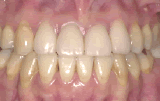

症例3/応用編

矯正歯科治療とかぶせものの歯科治療を併せて行った例です。

【歯科治療前】

【歯科治療後】